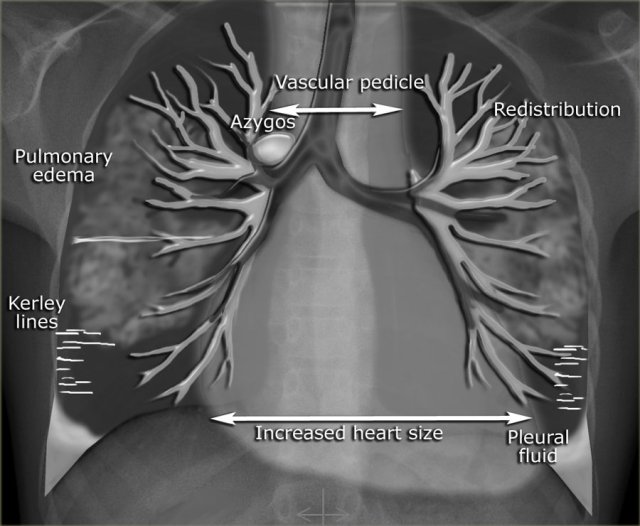

In the illustration on the left some of the features, that can be seen on a chest-film in a patient with CHF.

Increased pulmonary venous pressure is related to the pulmonary capillary wedge pressure (PCWP) and can be graded into stages, each with its own radiographic features on the chest film (Table).

This grading system provides a logical sequence of signs in congestive heart failure.

In daily clinical practice however some of these features are not seen in this sequence and sometimes may not be present at all.

This can be seen in patients with chronic heart failure, mitral valve disease and in chronic obstructive lung disease.